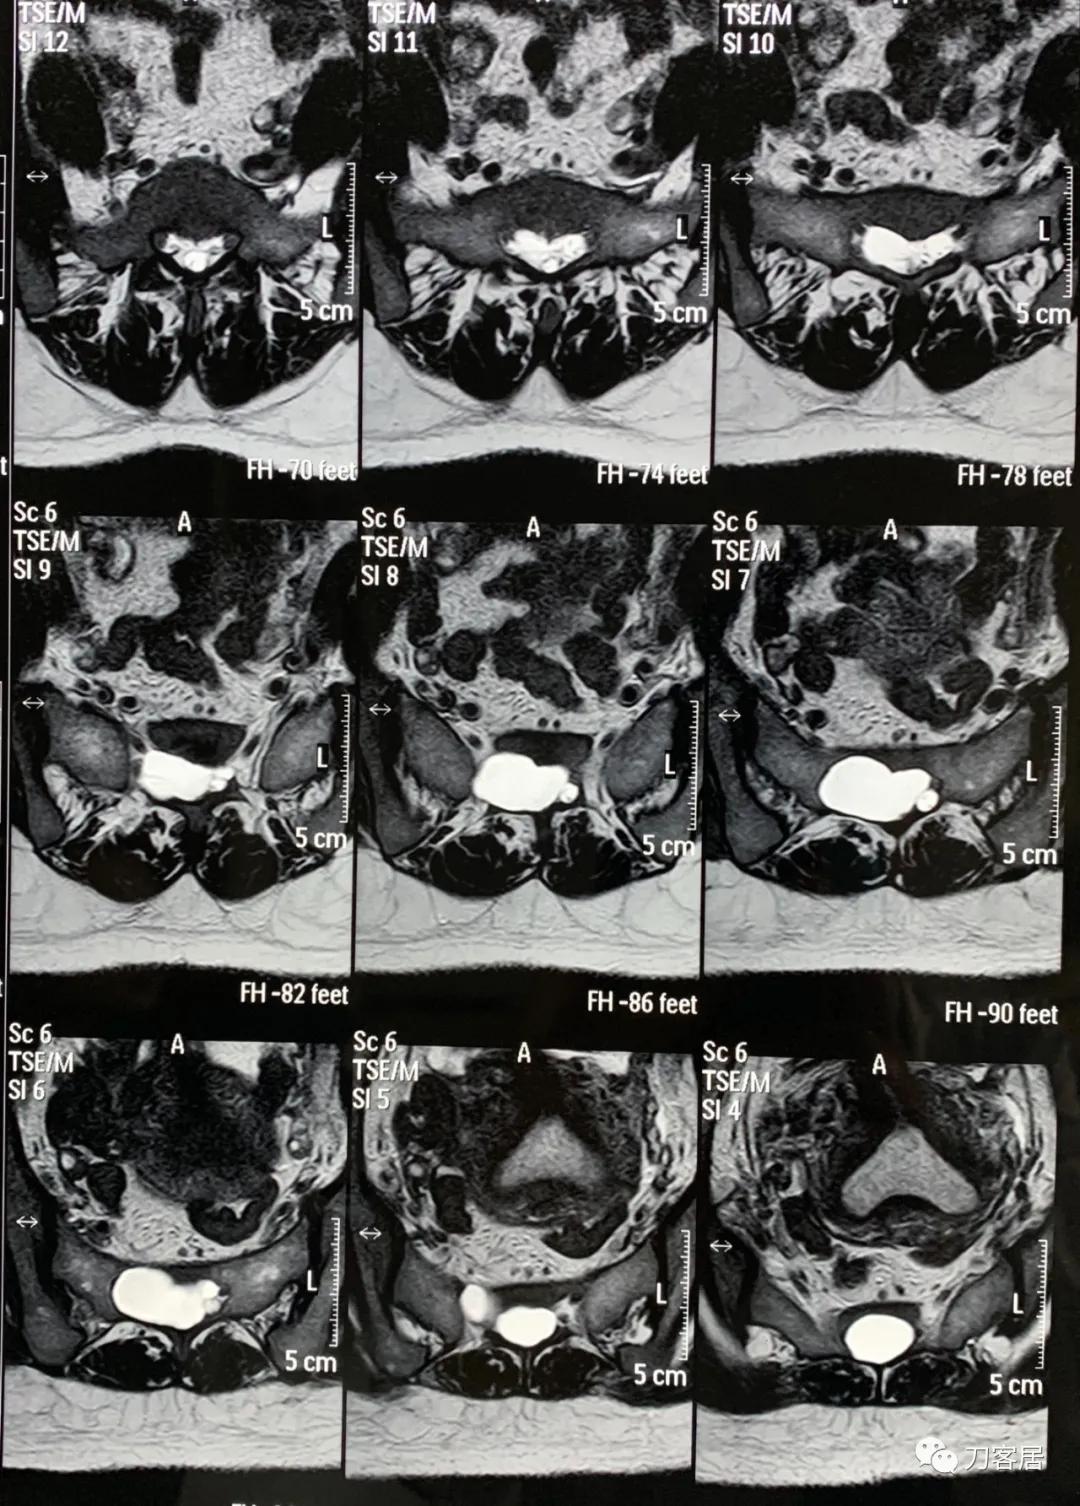

20160912患者骶管囊肿术后的腰骶椎磁共振